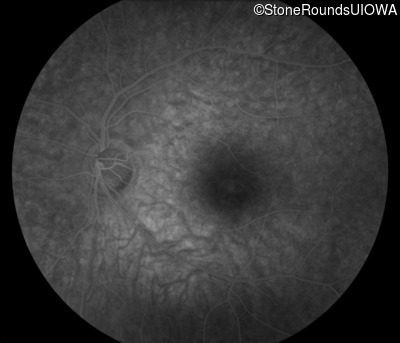

Infrared Fundus Photograph - Right - 20/25 +1

Exemplar